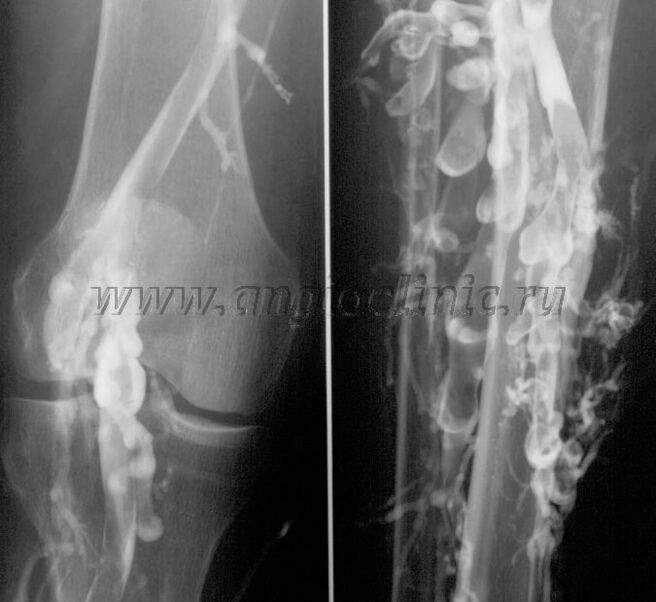

Kontrastní venografie

Obvykle postačuje ultrazvukové vyšetření pro úplnou diagnostiku žilní patologie, ale v některých případech je nutné studovat vztah mezi stavem hlubokého a povrchového žilního systému, zejména v případě relapsů křečových žil a sekundárních křečových žil.

K řešení těchto problémů se používá kontrastní rentgenové vyšetření. Safény se propíchnou a podá se kontrast. Pohyb kontrastu je sledován na monitoru rentgenového přístroje a jsou prováděny všechny potřebné testy a projekce. V současné době se venografie pro křečové žíly používá velmi zřídka.